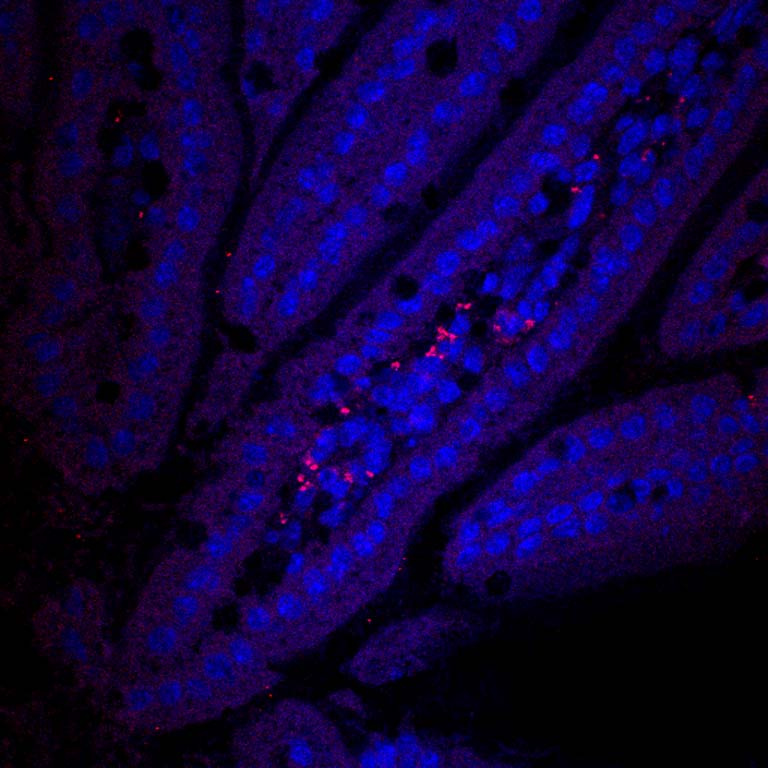

Nanoparticles (red) loaded with drugs are passing across the intestines into the bloodstream after oral ingestion. If loaded with insulin, the nanoparticles could be used in an insulin pill that could be taken by mouth for treatment of diabetes.